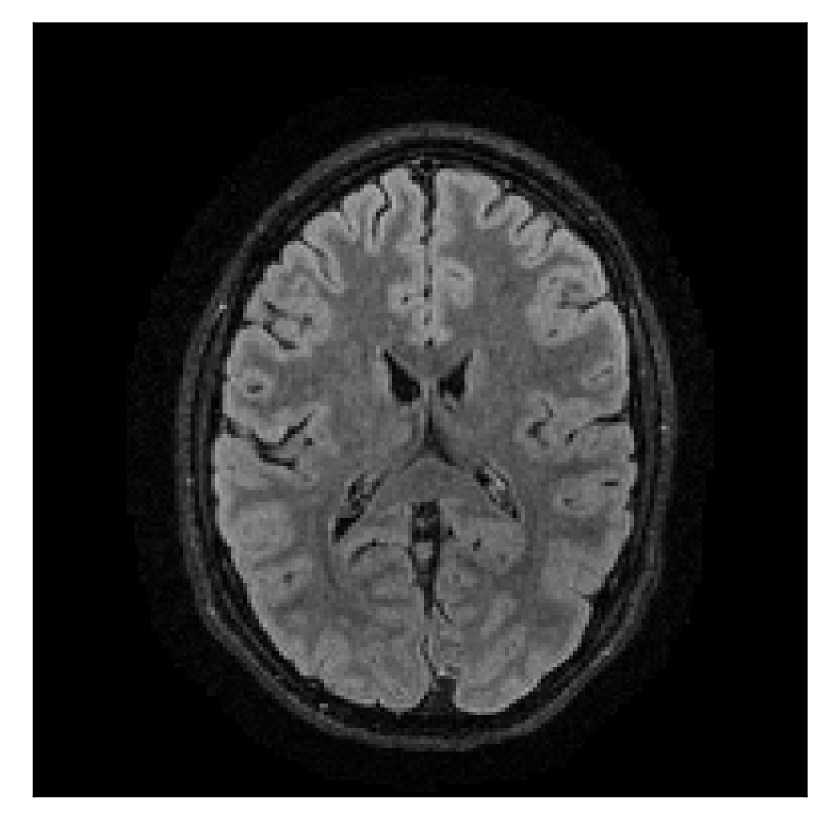

4.1 Experiment 1: robustness test

We gather the results for the robustness test described in Section 3.1 (volunteer 1) in Figures 2, 4, and 6 for motion corruption mechanisms associated to one, two, and five changes of position, respectively. Furthermore, we juxtapose the corrected images with varying degrees of corruption in Figure 8. We observe that the proposed method consistently ameliorates the corrupted scan. The quality indexes based on PSNR and SSIM show only a modest decrease in correction quality as a function of motion complexity (Figure 8).

| Section 3.1, Figure 2 | Sagittal | 23.94 | 27.95 | 0.7068 | 0.7936 |

| Coronal | 26.66 | 29.82 | 0.7653 | 0.8332 | |

| Axial | 25.40 | 30.16 | 0.7616 | 0.8490 | |

| Section 3.1, Figure 2 | T2-FLAIR | Completely corrected | Some blurring | No additional artifacts | Good grey white matter differentiation |